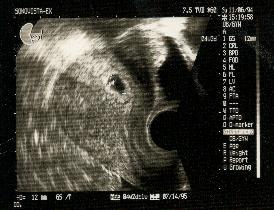

8週 胎嚢 小さい

妊娠8週目 8w0d 6d のエコー写真とエピソード 妊娠3ヶ月 Cozre コズレ 子育てマガジン

8w0d 胎嚢が狭い 卵黄嚢肥大 流産の兆候 43歳で4人目赤ちゃんを自宅出産しました

妊娠8週目 8w0d 6d のエコー写真とエピソード 妊娠3ヶ月 Cozre コズレ 子育てマガジン

妊娠8週目 8w0d 6d のエコー写真とエピソード 妊娠3ヶ月 Cozre コズレ 子育てマガジン

妊娠8週 3 6日 のエコー写真 体験談

妊娠8週目 8w0d 6d のエコー写真とエピソード 妊娠3ヶ月 Cozre コズレ 子育てマガジン

妊娠8週目 エコー写真や胎児の大きさ平均 つわりや流産症状 妊娠初期 All About

妊娠8週0日 8w0d の超音波 エコー 写真

妊娠8週目 8w0d 6d のエコー写真とエピソード 妊娠3ヶ月 Cozre コズレ 子育てマガジン

妊娠8週目 8w0d 6d のエコー写真とエピソード 妊娠3ヶ月 Cozre コズレ 子育てマガジン

妊娠8週 3 6日 のエコー写真 体験談

妊娠8週目 8w0d 6d のエコー写真とエピソード 妊娠3ヶ月 Cozre コズレ 子育てマガジン